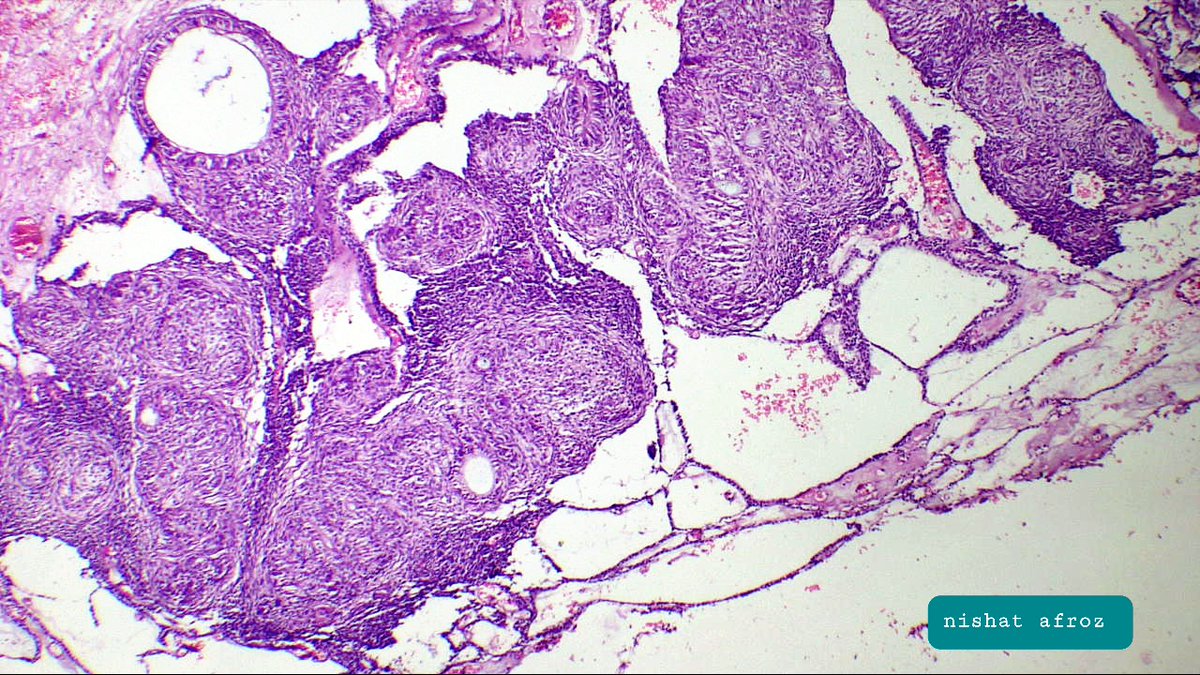

Spot diagnosis ! Male in 40's, radiolucent anterior maxillary( jaw) swelling. @DrNishatAfroz2 @nusrat_xahra @nucleololailo @PoloniaAntonio @asifwahab2012 @DrFahadAlam @premcharles #PathTwitter #oralpath #pathology